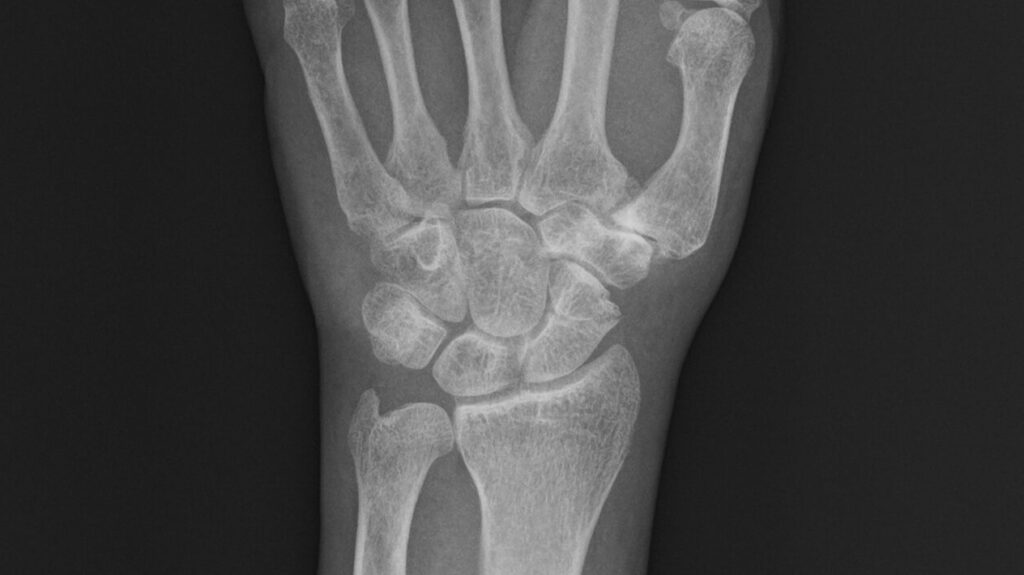

市内の病院を受診し、レントゲン撮影を行った結果、左手の舟状骨に骨折線が確認された。

舟状骨は、手首の親指側に位置する小さな手根骨で、転倒時に手をついた際の衝撃が集中しやすい部位である。

さらに、血流が乏しい骨であるため、骨癒合遅延や偽関節になりやすいことが医療者の間ではよく知られている。

下図は手術前の左手レントゲン写真で、中央の船状骨が砕けている様子が見える。

以下の5枚は再発後、手術直前に撮影されたレントゲン写真である。正面像では舟状骨遠位部に骨折線が見え、斜位像および側面像では骨片のずれが明確に確認できる。

/レントゲン写真を角度を変えて5枚撮影